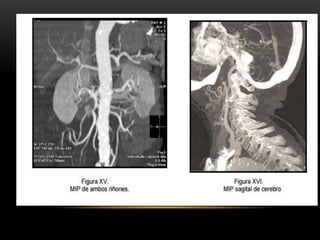

PROYECCIÓN DE MÁXIMA INTENSIDAD MIP

• Selecciona un rango de cortes bidimensionales

• Permite realzar las estructuras con mayor atenuación, facilita una visualización rápida y

efectiva de estructuras densas ( vasos contrastados y huesos)

• Este procedmiento se emplea principamente para examinar v. sang contrastados

PROYECCIÓN DE MÁXIMAINTENSIDAD MIP • Selecciona un rango de cortes bidimensionales • Permite realzar las estructuras con mayor atenuación, facilita una visualización rápida y efectiva de estructuras densas ( vasos contrastados y huesos)

• 62.

• Este procedmientose emplea principamente para examinar v. sang contrastados